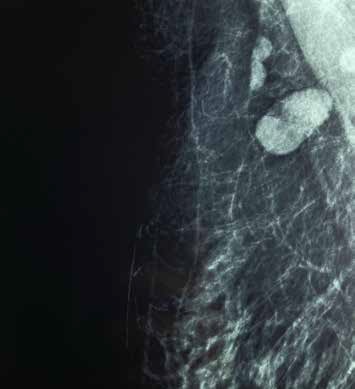

Tras haber comenzado la campaña de vacunación contra COVID-19, en diciembre de 2020, se ha observado una mayor incidencia en linfadenitis reactiva (ganglios axilares aumentados de tamaño) la cual, por lo general, de manera aislada no se observa con mucha frecuencia sin que se correlacione con otra patología en la mama. Sin embargo, realizar este tipo de hallazgos no deben pasar desapercibido ya que de acuerdo al contexto clínico de la paciente, se podría requerir de estudios complementarios como una resonancia magnética o incluso realización de biopsia para descartar algún proceso maligno o poder asegurar los cambios de benignidad asociada a esta vacuna y por lo tanto detectar de manera temprana la incidencia del cáncer de mama además de que este procedimiento dará tranquilidad  y certeza diagnóstica al médico a cargo y a la paciente.

Las vacunas que están autorizadas actualmente toman en cuenta la probabilidad de crecimiento de los ganglios axilares a la palpación, con inicio de presentación variable de acuerdo a la vacuna administrada siendo con mayor frecuencia para la vacuna Moderna y con menor incidencia la de Pfizer y AstraZeneca.

Habitualmente, el aumento de tamaño en los ganglios empieza entre los días 2-10 posterior a la aplicación de la vacuna, pudiendo detectarse estos cambios por imagen durante varias semanas posteriores. Es por esto que se considera necesario establecer protocolos de vigilancia en la linfadenopatia reactiva para lograr un manejo adecuado. Tomando en cuenta las siguientes recomendaciones:

• Pacientes con adenopatía axilar unilateral en screening se recomienda asignar BI-RADS 0 para evaluación y documentación de historia vacunal en caso de no contar con ello; BI-RADS 2 seguimiento clínico en ganglios aislados subclínicos en el contexto de vacunación reciente pudiendo corresponder a causa inflamatorio; BI-RADS 3 recomienda seguimiento posterior a segunda dosis de 4 a 12 semanas; BI-RADS 4 en caso de linfadenopatia persiste en intervalo de tiempo corto.

Actualmente se está realizando un protocolo de investigación en el servicio el cual realiza una identificación de pacientes que recibieron la vacuna contra COVID-19, caracterizando los ganglios axilares e identificando cambios en estos, en caso de encontrarlos se procede a dar un seguimiento a corto plazo en un periodo de tres y seis meses para así poder corroborar o descartar la benignidad asociada a esta aplicación.